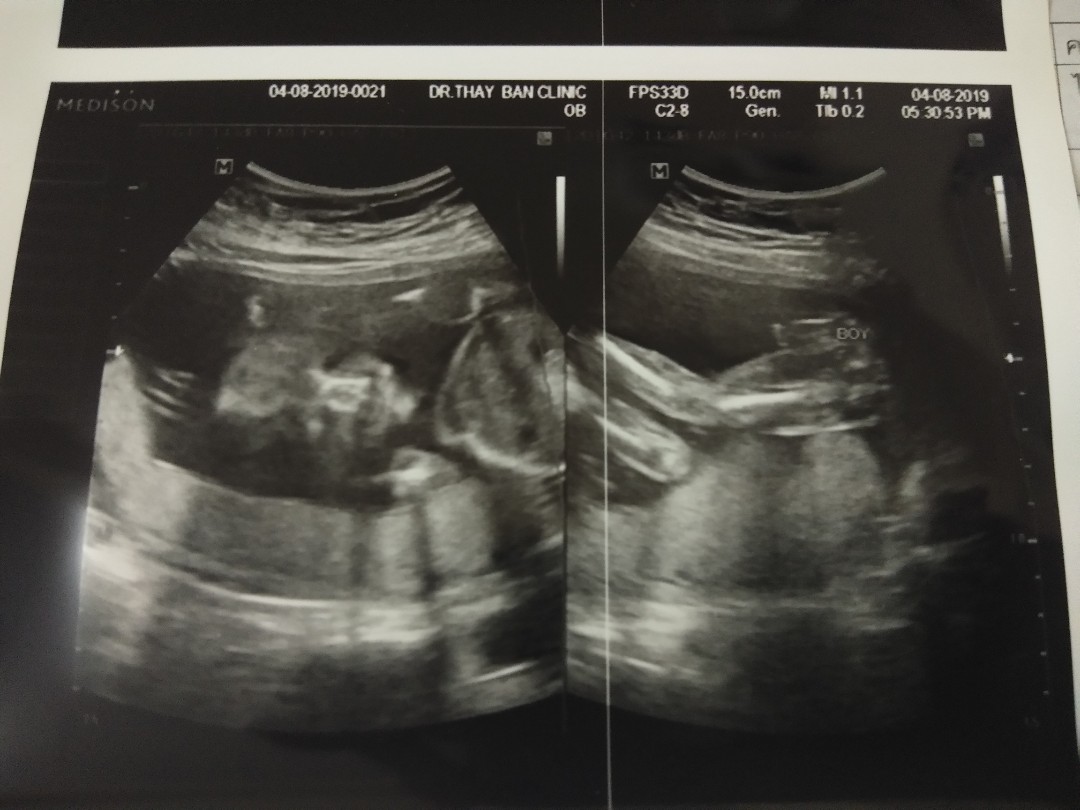

บ้านนี้ก้อลูกชายค่ะ30w++